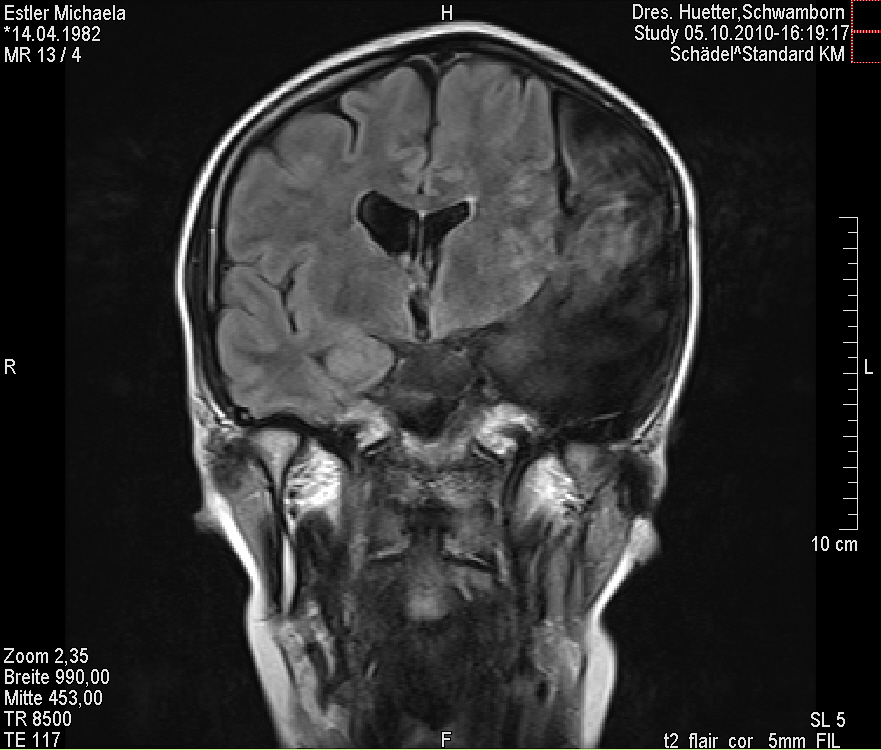

Ich stell euch hier noch eine kleine Galerie rein mit den neuesten Bildern. Ich denke es ist unübersehbar, dass das Ding gewachsen ist, außerdem mir meine komplette Hirnmittelline verschiebt und immer mehr Rücklagerung bekommt und Richtung Hirnsteuerungszentrum drückt. Meine häufiger auftretenden Stürze und Koordinationsprobleme werden also in naher Zukunft sicherlich nicht weniger werden und mein Doc und ich werden uns wohl auch zeitnah über eine weitere Klinik und eine mögliche weitere OP unterhalten müssen.